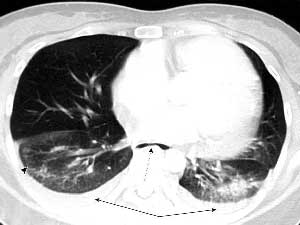

风湿性疾病肺受累常见影像学表现

非特异性

普通

急性间质性

淋巴细胞间质性

脱屑性

COP

类风湿结节